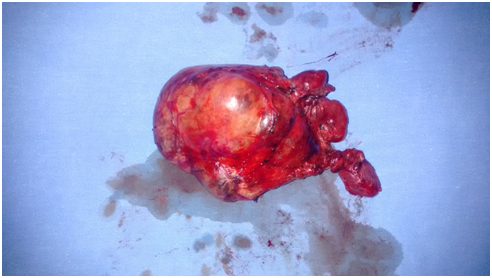

Thyroid gland was exposed. First left thyroid gland was mobilized followed by right thyroid gland. Bilateral recurrent laryngeal nerve was identified and preserved (Figure 3). The left thyroid mass was dissected. Sternotomy was done to enucleate the retrosternal mass from anterior mediastinum. Thyroid gland along with retrosternal mass was excised (Figure 4). Hemostasis was achieved. Drains were kept and closure was done in layers. Postoperatively patient was started on Tab Neomaracazole 2.5mg and Tab Inderal 80mg. Postoperative T4 was 145nmol/L. Patient was discharged on 4th postoperative day.

Figure 4 Thyroid gland along with retrosternal mass was excised.